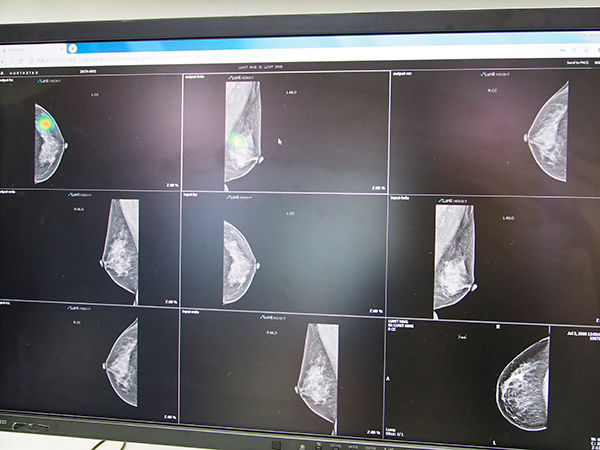

使用方法は簡単で,NorthStarに送信されたデータのワークリストから参照したいデータを選択すると,そのデータに適したAIアルゴリズムが自動で表示され,利用したいアルゴリズムを選ぶとすぐに解析結果が表示される。例えば,胸部CTから肺結節を検出するAIアルゴリズムでは,対象検査を選ぶと瞬時に検出された結節の位置やCT値,サイズが画像上に示される。医師は,それぞれの検出結果について「accept」や「reject」を判断してフィードバックすることでAIアルゴリズムが学習し,より解析精度が向上していく。また,NorthStarにデータが送られた時点で,データに適したAIアルゴリズムが動き,脳出血などの危険度が高いと予想されるデータはワークリストの上部に表示され,医師は救急症例として優先して画像を確認することができる。

ブースでは,肺結節検出や脳出血検出のほか,マンモグラフィの乳腺密度解析,心臓MRIの心機能解析,整形外科領域では骨折検出やインプラント手術プランニング支援など,さまざまな領域を対象とした多彩なAIアルゴリズムが紹介された。

マンモグラフィの乳腺密度解析

マンモグラフィの乳がん検出